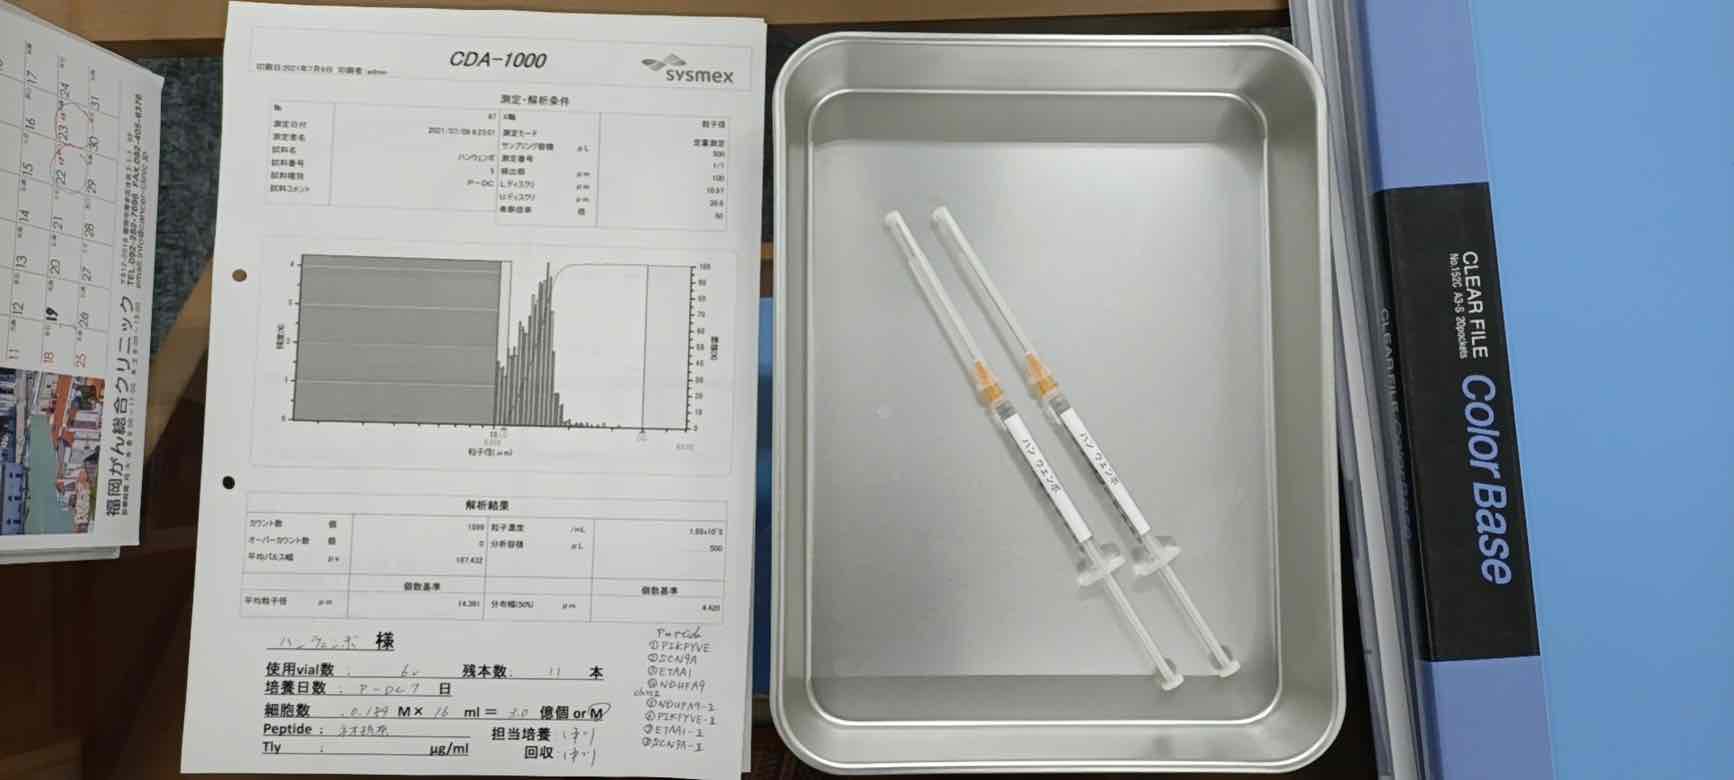

国内的研究机构和专家,大家可以咨询一下